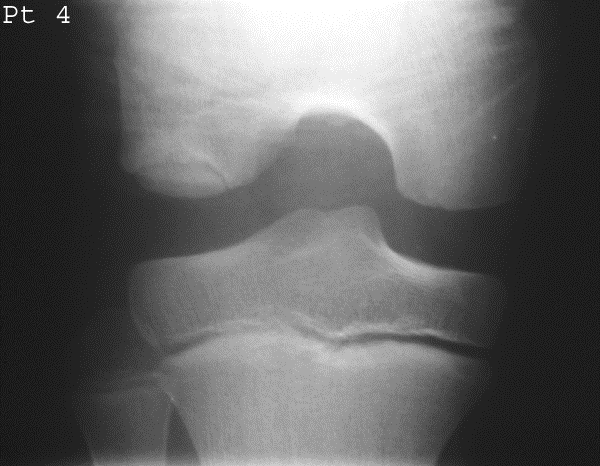

What is Osteochondritis Dissecans?

Avascular necrosis of subchondral bone fragments, often traumatic.

Who is most affected by Osteochondritis Dissecans?

Adolescents (11–20), athletes.

Most common site of Osteochondritis Dissecans?

Medial femoral condyle (75%).

Symptoms of Osteochondritis Dissecans?

Joint effusion, clicking, locking, tenderness.

How is it diagnosed radiographically?

MRI/CT for cartilage lesions; X-ray shows fragments and site of origin; tunnel view for knee.